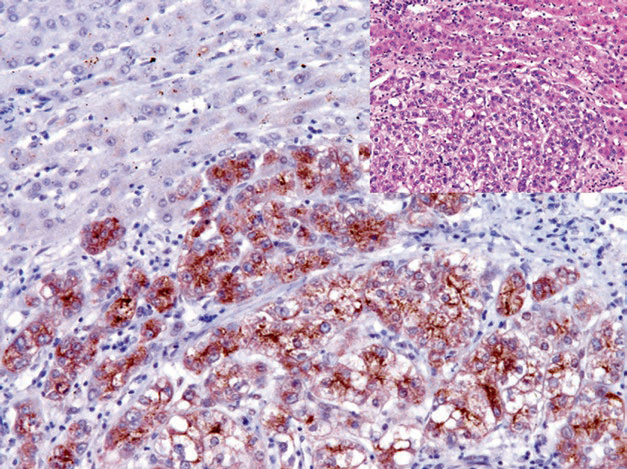

Figure 1. Hepatocellular carcinoma, immunohistochemistry CD34, sinusoidal endothelial cells positive.

Figure 3. Hepatocellular carcinoma, immunohistochemistry Glypican-3 positive; non-neoplastic liver tissue in the background is negative.

Mai Mai: “Arginase-1 is a sensitive and specific marker for hepatocellular adenoma and hepatocellular carcinoma, and can be combined with Glypican-3 and Hepatocyte for the differential diagnosis of primary hepatocellular carcinoma from metastatic tumors and cholangiocarcinoma.。Glypican-3 is expressed in embryonic liver, kidney, lung tissues, and the trophoblast layer of placental tissue, while other normal tissues do not express it,Positive expression can be seen in neoplastic tissues such as hepatocellular carcinoma, yolk sac tumor, choriocarcinoma, and melanoma. Combined use with CD34 can help differentiate benign from malignant hepatocellular tumors.”